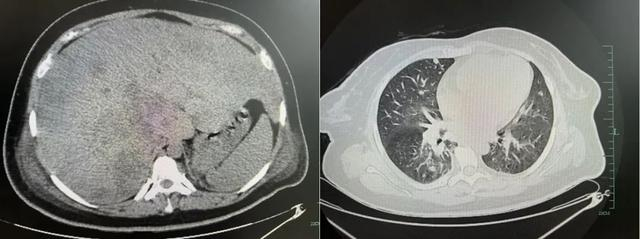

检查提示,杨女士总胆红素超300μmol/L(参考范围:5.13~22.24μmol/L),肝脏重度肿大,肝内多发占位,转移瘤考虑;肺部提示,两肺多发结节灶,转移瘤考虑;腹部B超提示,胆囊实质性占位,胆囊癌考虑,最终诊断为胆囊恶性肿瘤IV期,没有手术、化疗等机会,只能止痛姑息对症治疗,预后非常差。